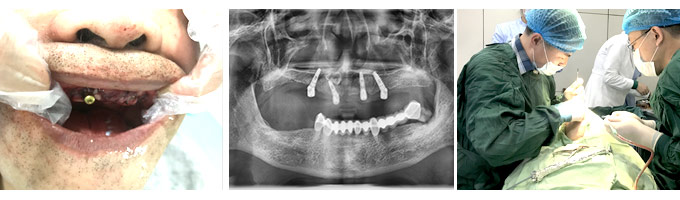

牙齿种植

Dental implants

缺失了一颗牙一定要尽早的进行修复治疗,以免造成周围的牙齿也跟着出现松动和脱落。种植牙的价格 一直是大家比较关注的,那么,无锡种一颗牙价格是多少?

种植牙